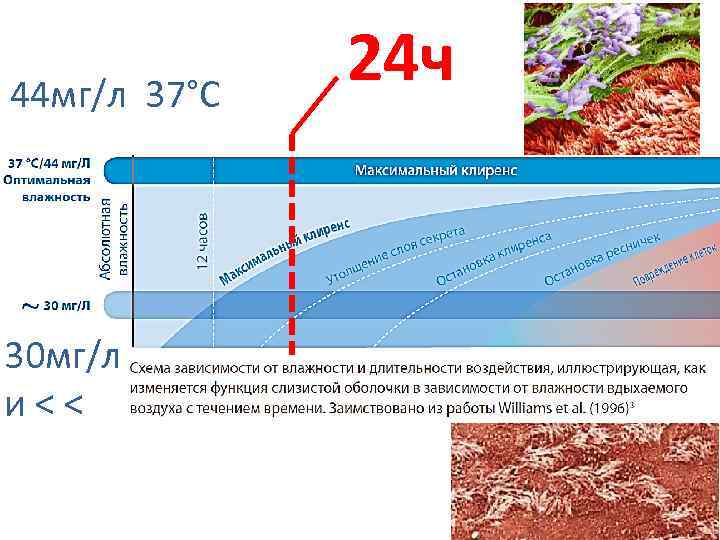

44 мг/л 37°С 30 мг/л и < <

44 мг/л 37°С 30 мг/л и < <

Факторы риска : Недостаточное увлажнение дыхательной смеси При длительной ИВЛ (> 24 ч) Мы используем только увлажнители испарительного типа

Факторы риска : Недостаточное увлажнение дыхательной смеси При длительной ИВЛ (> 24 ч) Мы используем только увлажнители испарительного типа

44 мг/л 37°С 30 мг/л и < < 24 ч

44 мг/л 37°С 30 мг/л и < < 24 ч